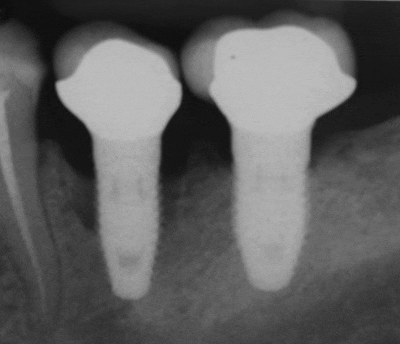

실제 임플란트와 상부 구조 사이에 틈과 구멍이 있는 경우

이 안으로 세균이 구강 침투하고,

나중에 이 병균들은 관련 조직으로 돌아와서 임플란트 주위염을 발병시킵니다.

이러한 과정으로

임플란트 주위염으로 인해 위의 이미지와 같이 잇몸 뼈가 점점 소실됩니다.

엑스레이를 촬영해 육안으로 보기 어려운 뼈의 상태와 임플란트 주변의 증세를

검진하게 됩니다.